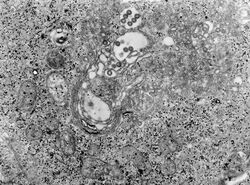

TEM micrograph of tissue infected with Rift Valley fever virus